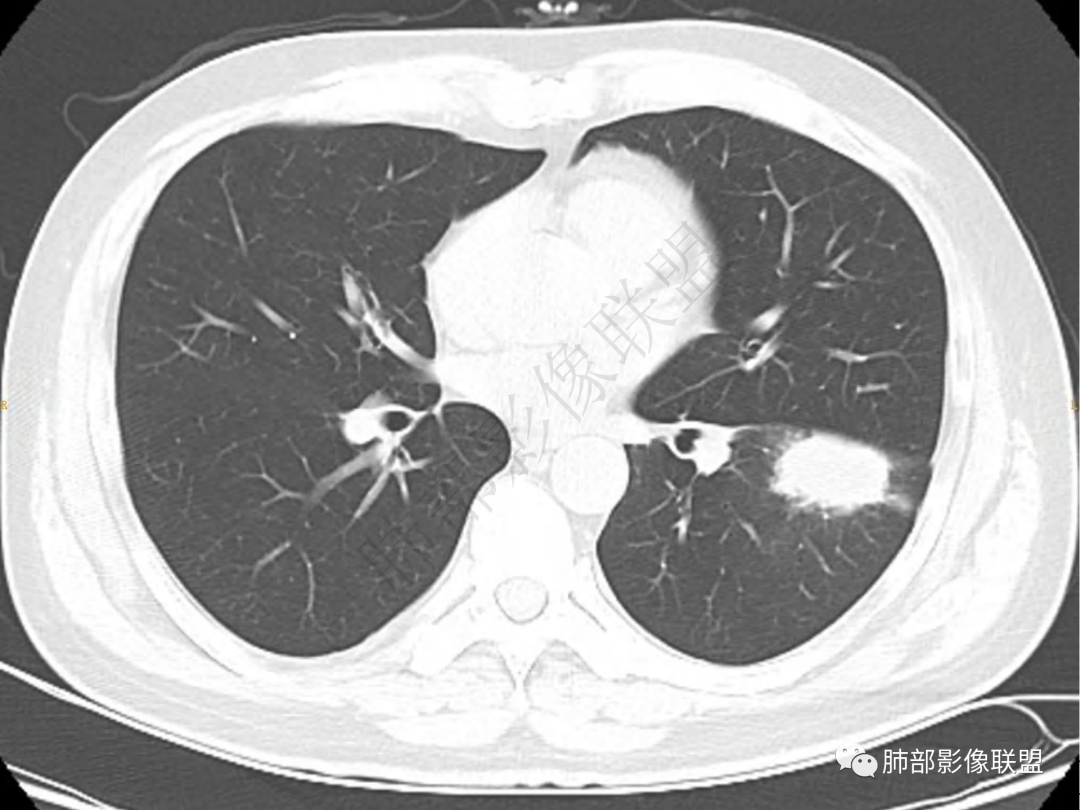

1.中年男性,咳嗽咳痰20余天,间断咯血2周

2.左肺下叶团片影,跨背段及内前基底段,实性部分类椭圆形,密度不甚均匀,可见毛刺及棘状突起,未见典型分叶及胸膜凹陷。病灶上下缘可见相应肺段支气管旁进侧出,管壁轻度增厚,未见狭窄阻塞。

3.周边较大范围磨玻璃影,边界相当模糊,小叶增厚明显。注意叶裂另一侧、左肺舌段亦可见磨玻璃影及增厚的小叶间隔。未见明确卫星病灶。

1.病灶不够密实,没有典型分叶,收缩乏力等,支气管未见截断等,缺乏一般肿瘤性肿块特征。

2.周围磨玻璃影边界不清缺乏限制,甚至“激惹”到相邻肺叶,也许提示较明显的炎性水肿。

正如多数老师分析到的,本例病灶炎性特点比较明显。